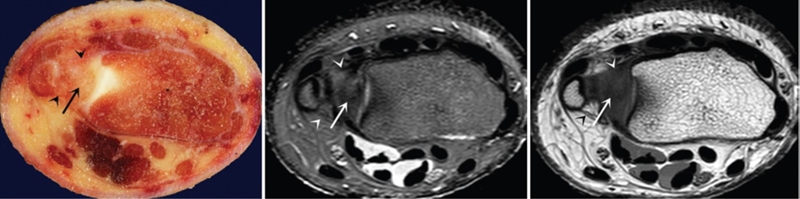

ⅠA,TFCC中心穿孔,A、B三角软骨盘正常弓形低信号缺损;C轴位显示三角软骨盘中心的高信号区与D关节镜一致

ⅠB,TFCC尺侧撕裂;TFC尺侧附着处信号增高

ⅠC,尺三角韧带撕裂

ⅠD,TFC桡侧撕裂,桡侧附着处及桡尺关节处信号增高

ⅡA,TFC局部变薄,但结构完整

ⅡB,TFC局部变薄,但结构完整,月骨软骨厚薄不均

ⅡC,TFC中心撕裂,月骨软化,月三角韧带完整

ⅡD,TFC中心撕裂,月骨软化,月三角韧带缺如

图30 ⅡE,TFC中心撕裂,月骨、尺骨软骨软化,月三角韧带缺如,桡尺关节骨质增生